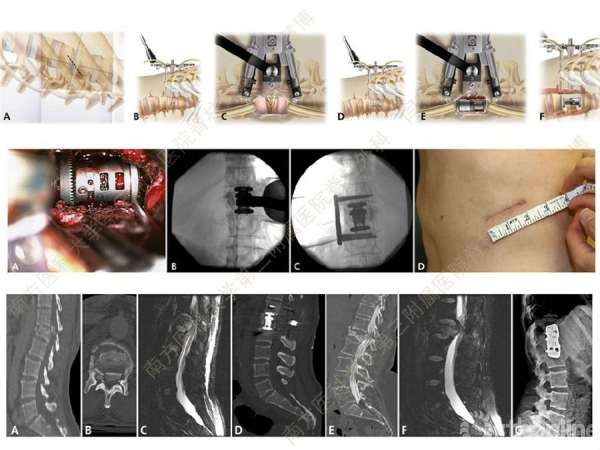

胸腰椎骨折是指由于外力造成胸腰椎骨质连续性的破坏,在如车祸、高处坠落等意外事故中,是最常见的脊柱损伤。老年患者由于本身存在骨质疏松,甚至有可能因为一些如滑倒、跌倒等低暴力因素导致胸腰椎骨折。胸腰椎骨折患者常合并神经功能损伤,且由于致伤因素基本为高能损伤,常合并其他脏器损伤,这为治疗带来了极大的困难和挑战。针对胸腰椎骨折,南方医科大学第三附属医院闫慧博教授介绍了他们运用微创方法治疗的经验。